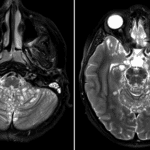

Indication: Follow-up hydrocephalus

- Numerous T2/FLAIR hyperintense leptomeningeal lesions along the surface of the brainstem, cerebellum, hippocampi, thalami, basal ganglia, and inferior right frontal lobe

- Associated mass effect on the fourth ventricle without hydrocephalus

- Rounded subcortical T2/FLAIR hyperintense lesion in the right frontal lobe

- Right frontal approach ventriculostomy catheter with tip near the foramen of Monro

- Prior suboccipital craniectomy

Diffuse leptomeningeal glioneuronal tumor